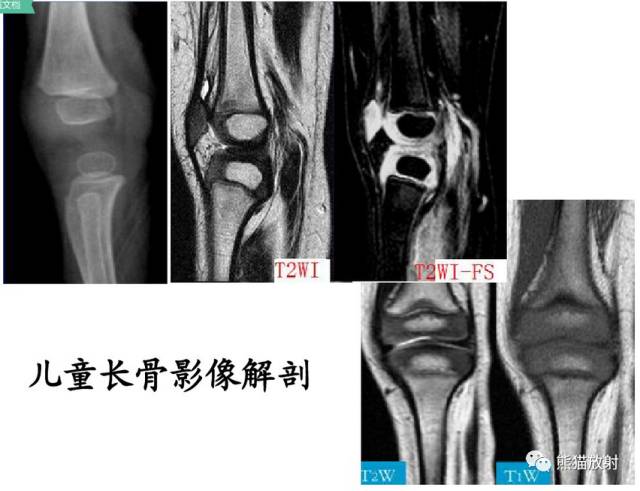

骨骺骨折 Physeal fractures

Salter-Harris 分型

I型:骨骺分离(有或无移位,多不引起生长障碍)

II型:骨骺分离伴干骺端骨折(最多见)

III型:骨骺骨折(属于关节内骨折)

IV型:骨骺和干骺端骨折(较多见,关节内骨折,易引起发育障碍和关节畸形)

V型:骺板挤压性损伤(少见,多在晚期发生生长障碍时才能作出诊断)